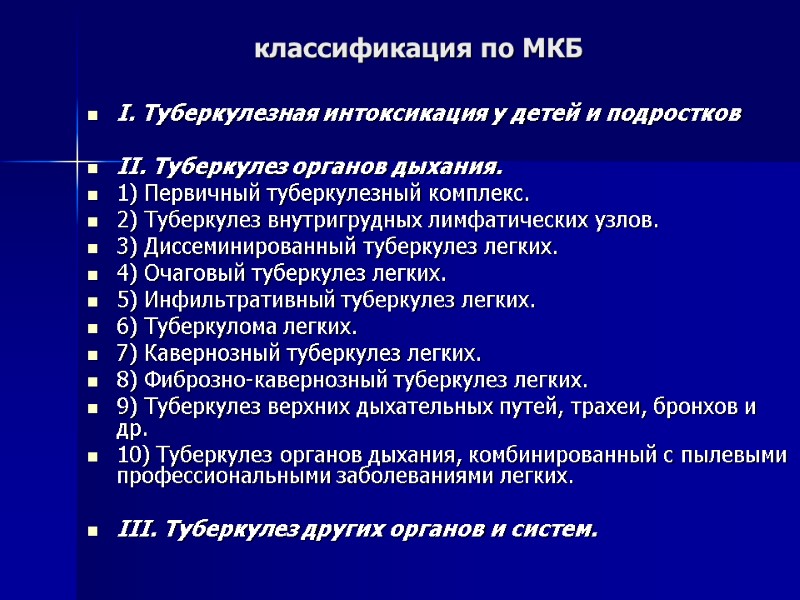

классификация по МКБ I. Туберкулезная интоксикация у детей и подростков II. Туберкулез органов дыхания. 1) Первичный туберкулезный комплекс. 2) Туберкулез внутригрудных лимфатических узлов. 3) Диссеминированный туберкулез легких. 4) Очаговый туберкулез легких. 5) Инфильтративный туберкулез легких. 6) Туберкулома легких. 7) Кавернозный туберкулез легких. 8) Фиброзно-кавернозный туберкулез легких. 9) Туберкулез верхних дыхательных путей, трахеи, бронхов и др. 10) Туберкулез органов дыхания, комбинированный с пылевыми профессиональными заболеваниями легких. III. Туберкулез других органов и систем.